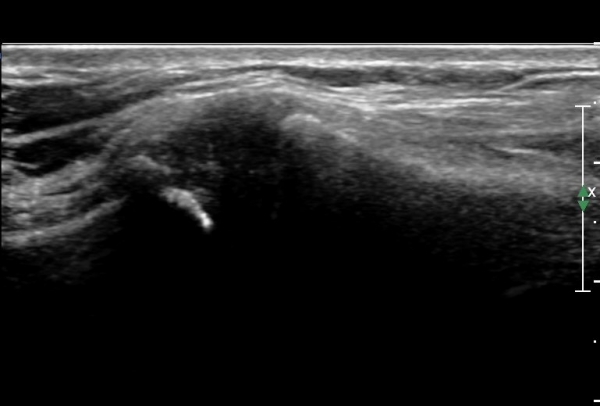

¿ìÃø Èä°ñ¼â°ñ°üÀýÃÊÀ½ÆÄ°Ë»ç¿¡¼­ °üÀýÀÇ ÅðÇ༭ º¯È­°¡ °üÂûµÊ(»çÁø 3, 4).

ÆÄ¿öµµÇ÷¯°Ë»ç¿¡¼­ °üÀýÀýºÎÀ§ Ç÷·ùÁõ°¡°¡ °üÂûµÊ(»çÁø 5).

out of plane ÃÊÀ½ÆÄÀ¯µµÇÏ °üÀý³» Áֻ翡¼­ °üÀý³»¿¡ ÁÖ»çħÀ» È®ÀÎÇϰí(»çÁø 6)

Áֻ縦 ½ÃÇàÇÔ(÷ºÎ µ¿¿µ»ó).